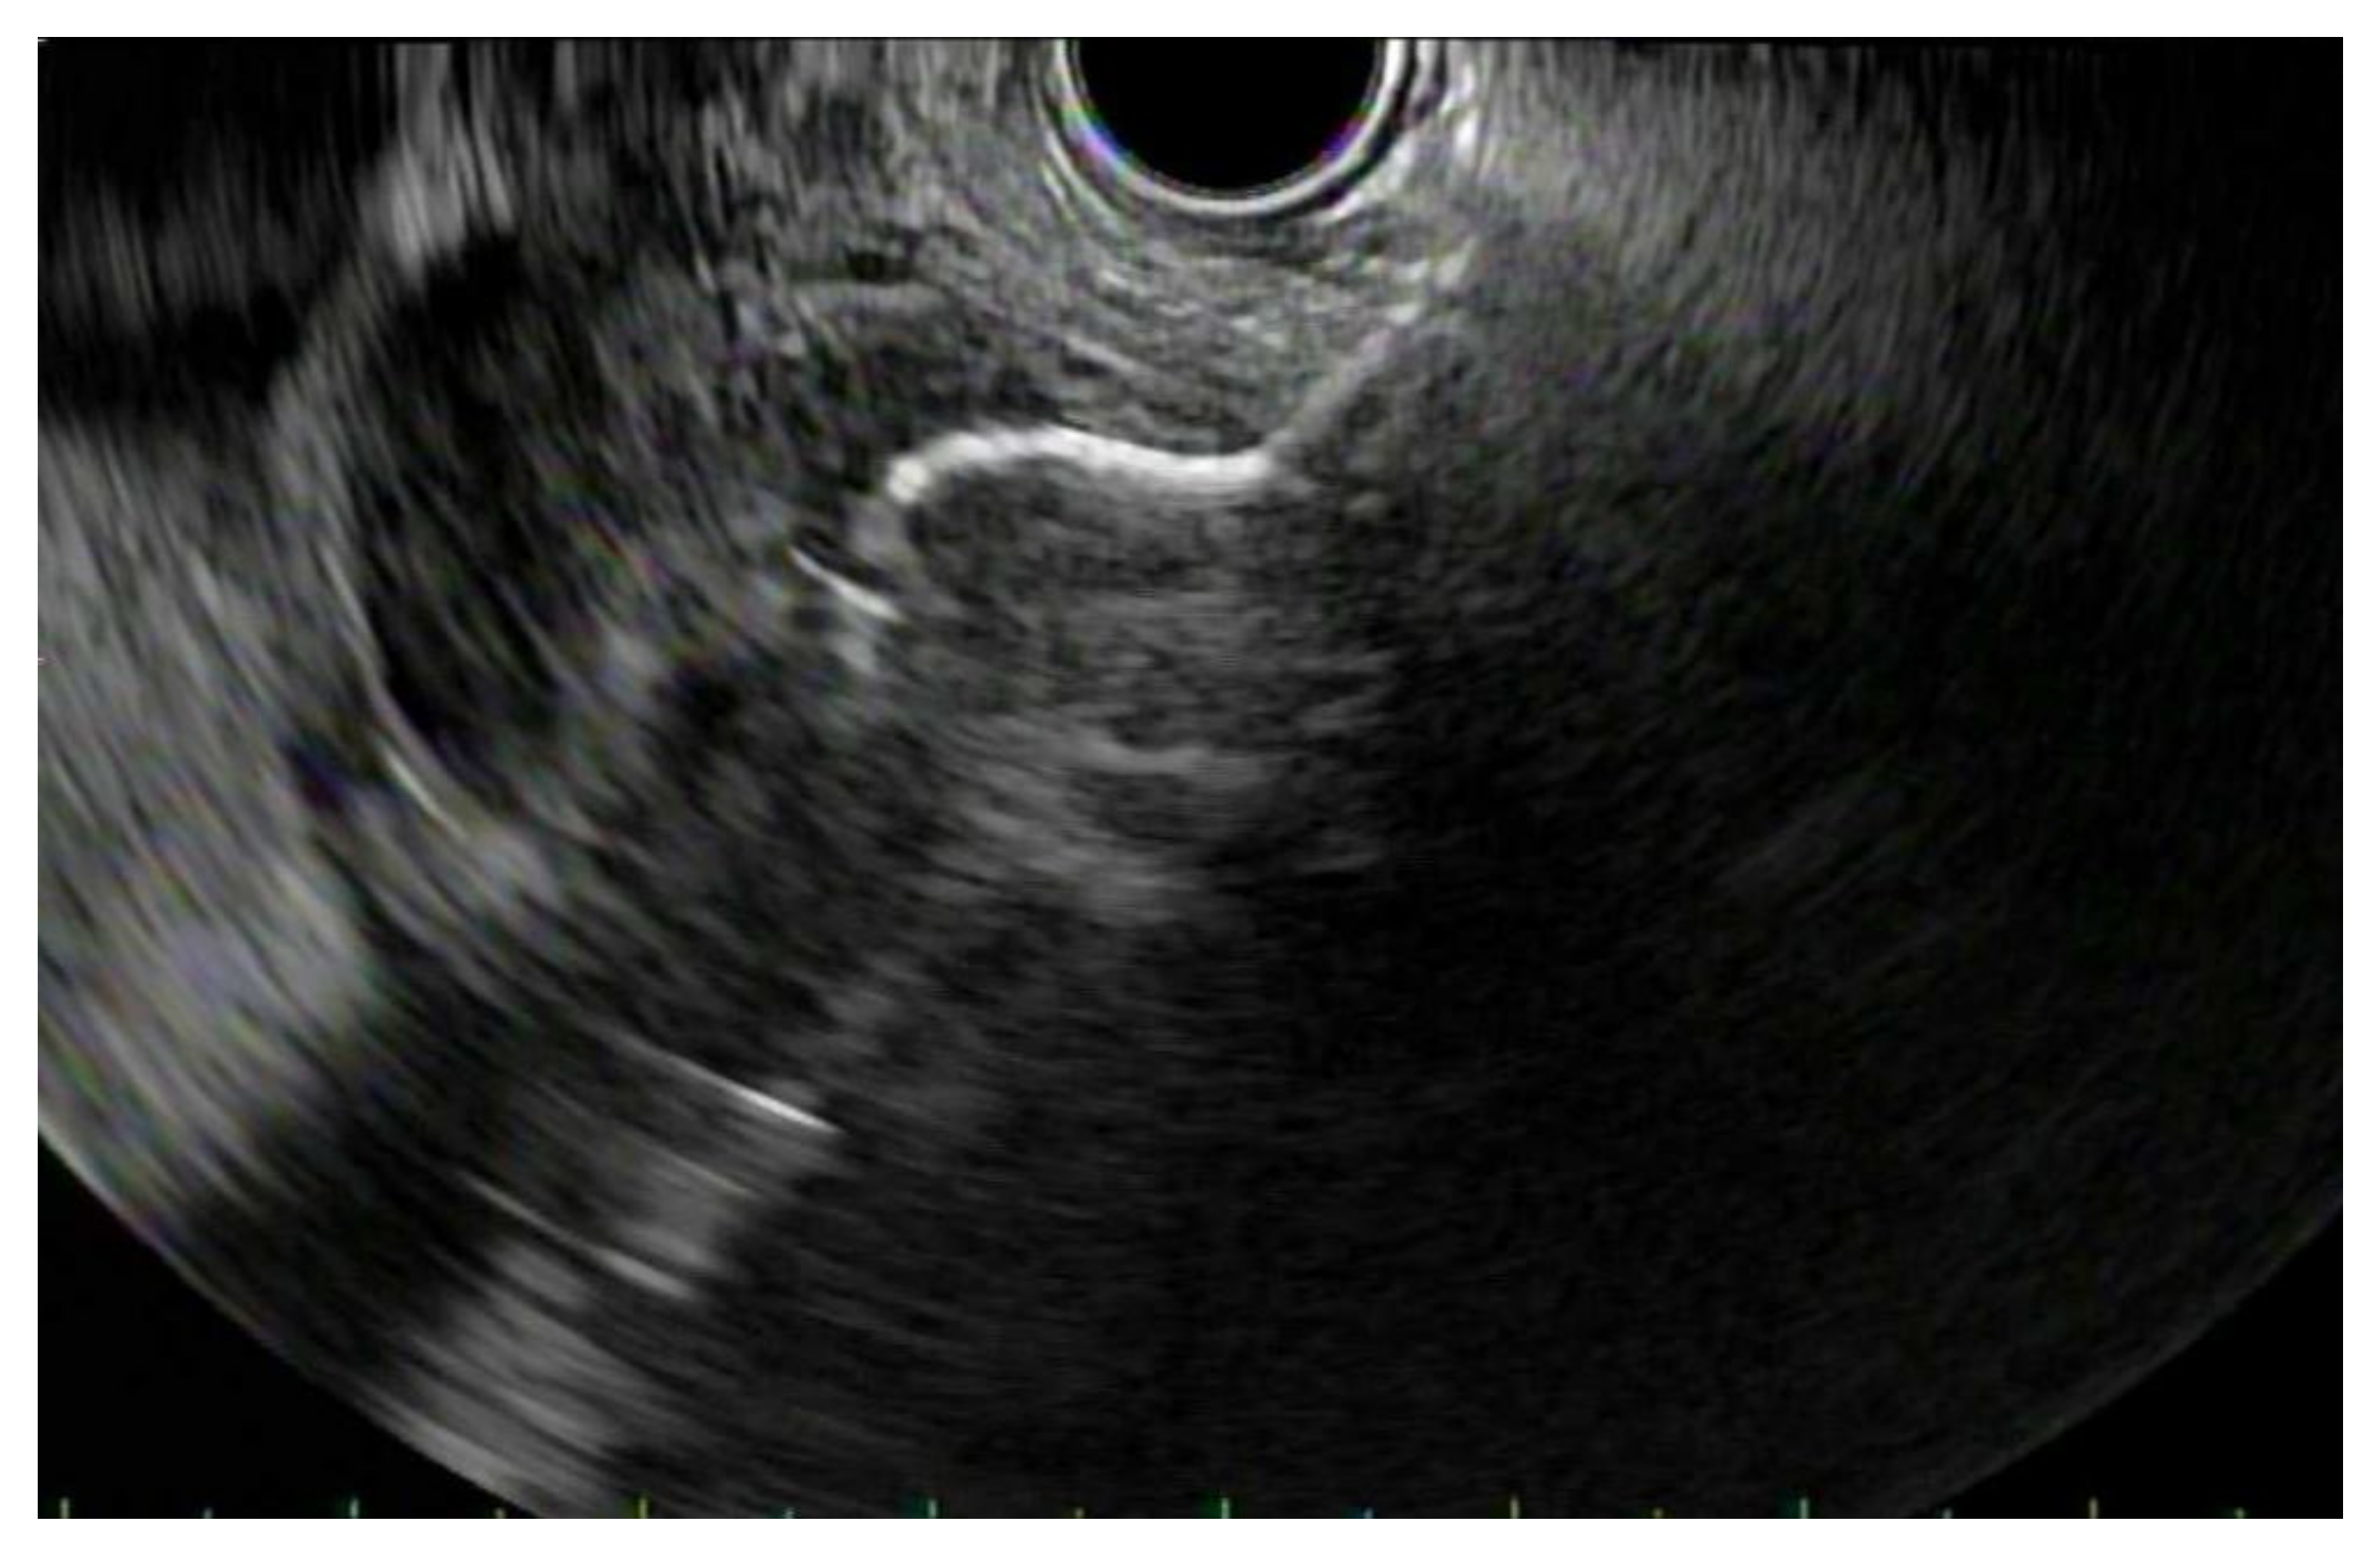

2. Patient Selection and Diagnostic Approach

3. Diagnostic Tests

3.1. EUS vs. Percutaneous Biopsy